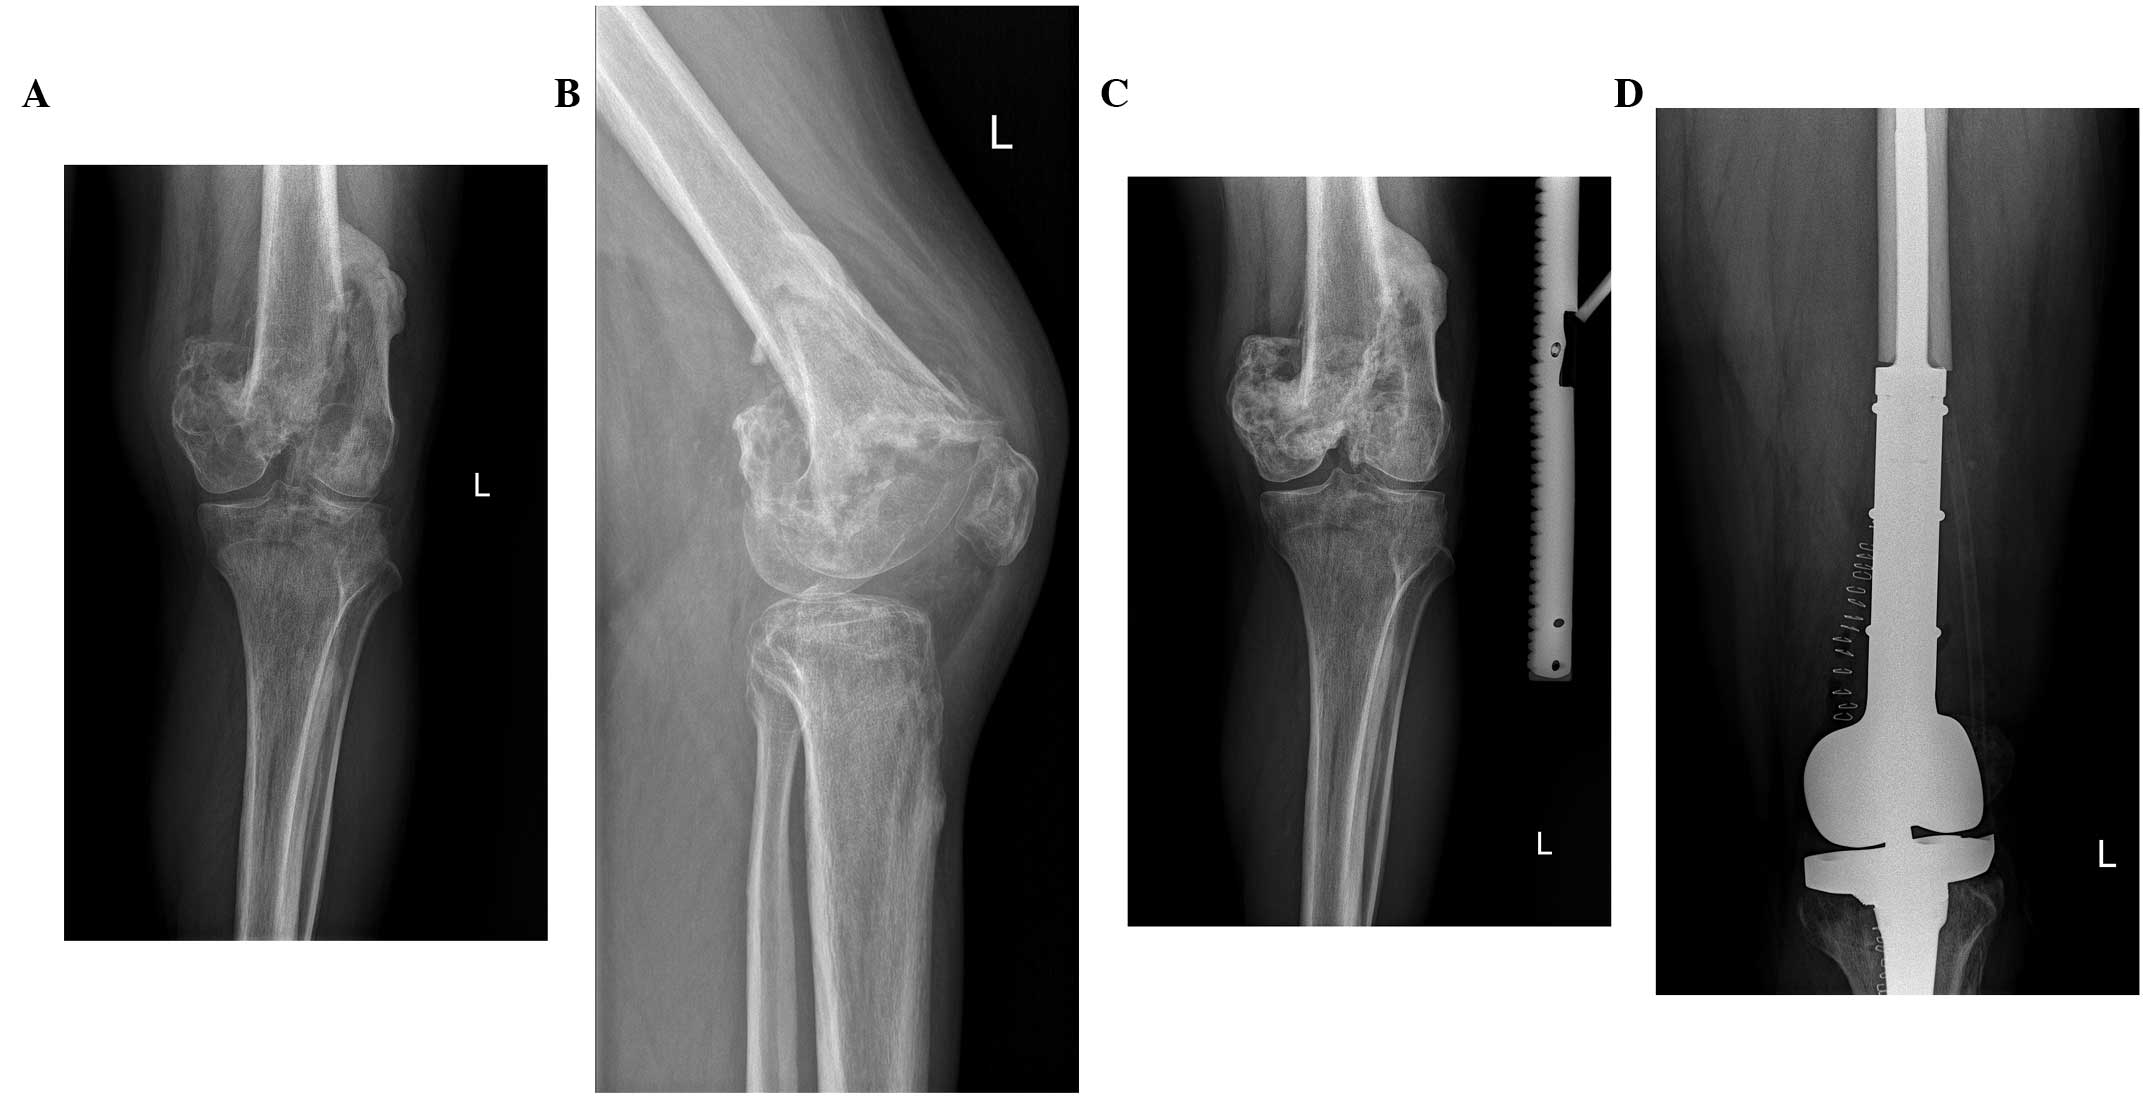

A 23 Year Old Woman With A Giant Cell Tumor Of Bone Treated With En Download Scientific Diagram